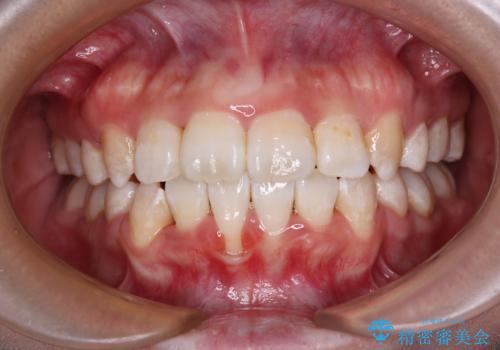

半年ほどで前歯のデコボコは改善され、汚れの溜まりやすさは解消されました。

抜歯スペースを閉じるために期間がかかりましたが、当初予定通り2年強で終えることができました。